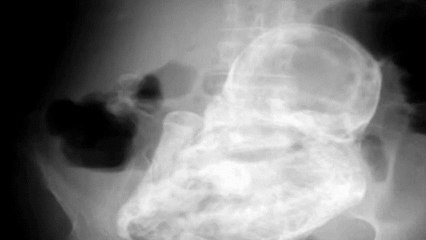

Des médecins mexicains ont été bafoués par la découverte d’un foetus mort à l’intérieur du corps d’une femme de 84 ans qui le portait depuis 40 ans.